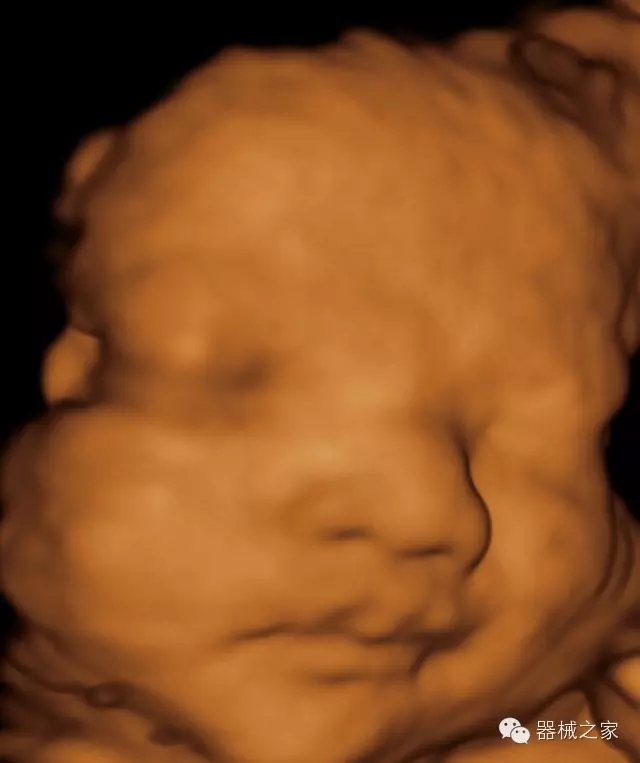

經(jīng)典產(chǎn)品:S8EXP

臨床圖片賞析

產(chǎn)品特點

·高效3D/4D成像技術:高速的4D幀頻,豐富的3D成像模式,智能斷層切片功能;